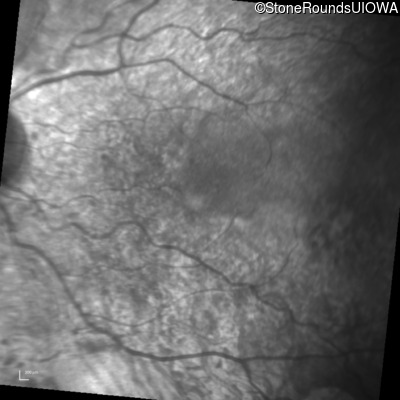

Infrared Fundus Photograph - Left - 20/32

Exemplar